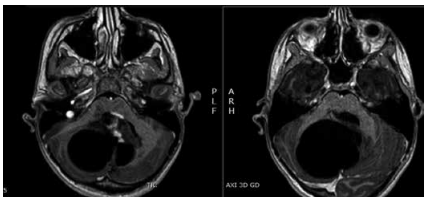

Um jovem de 14 anos de idade deu entrada no pronto-socorro com queixa de cefaleia persistente. A anamnese evidenciou que a cefaleia era matinal, com dois meses de evolução e obtinha alívio após vômitos. O paciente apresentou dificuldades de equilíbrio e de coordenação motora. Ele estava consciente, orientada, com marcha atáxica. O paciente apresentava incoordenação do membro superior ao realizar a prova índice-nariz. Foi realizada a ressonância do encéfalo com contraste, conforme ilustra a imagem a seguir.

Enunciado 4131012-1

Ressonância magnética axial 3d com contraste.

Com base nessa situação hipotética, e em relação à lesão apresentada acima, é correto afirmar que se trata de um